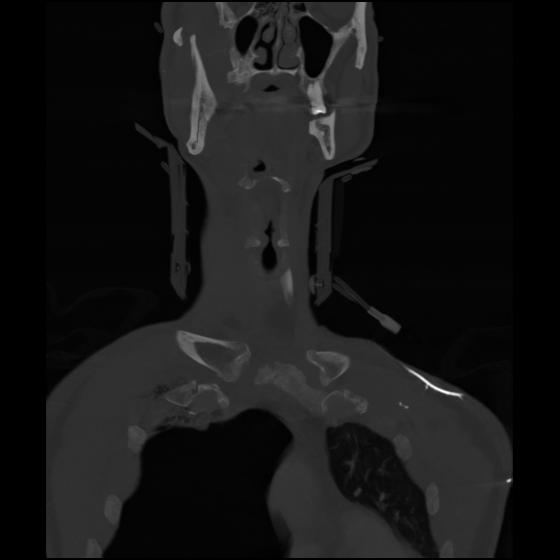

23 ANGIO,CE,Cor-MIP,5.000,ANGIO,Cor-MIP,